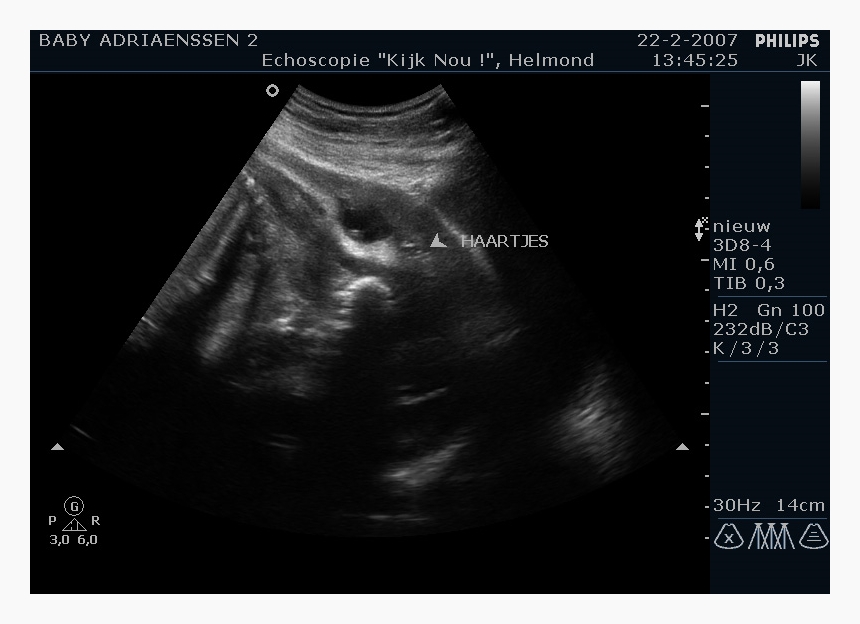

妊娠2か月までの赤ちゃんを「胎芽(たいが)」といいます。まだ受精卵ですから、超音波でも豆粒大の姿がかすかにとらえられるくらいの大きさ。人間っぽいかたちはしていません。

7週目くらいになると、超音波で心臓の拍動が確認できるようになります。手足らしきものもみえてきます。